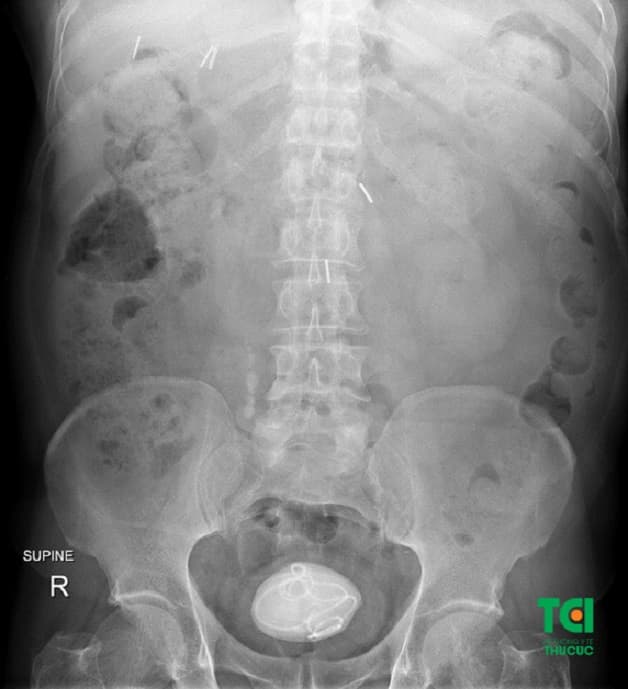

Sỏi phát triển với kích thước lớn nằm trong bàng quang của bệnh nhân